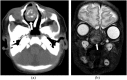

Hamartomas are tumours composed of mesenchymal tissues such as cartilage, fat, connective tissue and smooth muscle and can be found in virtually any organ system. These masses commonly develop sporadically, but are also seen in certain syndromes such as tuberous sclerosis or Carney triad. While their imaging appearance varies depending on the organ they arise from, findings are usually unique and a diagnosis can be confidently made. Radiologists must be aware of the clinical and imaging presentations of these lesions with the particular goal of avoiding unnecessary studies or invasive procedures. Furthermore, knowledge of common syndromic entities is crucial, as the radiologist may be the first to suggest the diagnosis.

- Saleem SN, Said AH, Lee DH. Lesions of the hypothalamus: MR imaging diagnostic features. Radiographics 2007; 27: 1087–108. doi: https://doi.org/10.1148/rg.274065123 - DOI - PubMed

- Glastonbury CM, Osborn AG, Salzman KL. Masses and malformations of the third ventricle: normal anatomic relationships and differential diagnoses. Radiographics 2011; 31: 1889–905. doi: https://doi.org/10.1148/rg.317115083 - DOI - PubMed